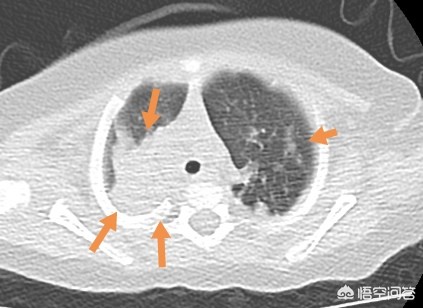

像这位小朋友,重症支原体肺炎,由于粘稠的分泌物堵塞气道,炎症吸收很缓慢,后来通过支气管镜灌洗,清理了气道的毒素和分泌物。